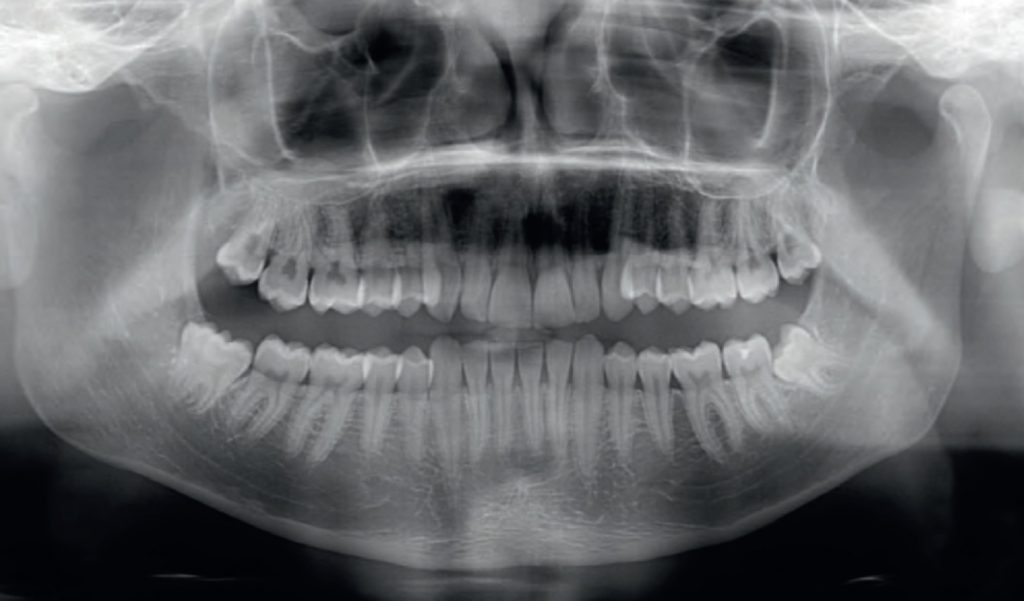

Streszczenie: Wstęp. Dystalizacja jest skuteczną metodą stosowaną do korekty II klasy zębowej oraz do uzyskania miejsca dla stłoczonych zębów przednich. Klasycznym aparatem wykorzystywanym do dystalizacji jest wyciąg zewnątrzustny. Alternatywę stanowią aparaty wewnątrzustne, do których należy aparat Carriere Motion. Siła dystalizująca górne zęby w segmencie bocznym pochodzi z wyciągu międzyszczękowego rozpiętego pomiędzy dolnym trzonowcem a dystalizatorem. Cel. Celem pracy jest przedstawienie przypadków leczonych wewnątrzustnym aparatem do dystalizacji Carriere Motion. Opis przypadków. W artykule zaprezentowano leczenie dwóch młodocianych pacjentów, u których uzyskano I klasę zębową. Wnioski. Carriere Motion jest skutecznym aparatem do dystalizacji i dystorotacji pierwszego trzonowca. Zakres dystalizacji jest porównywalny z przypadkami, w których wykorzystano miniimplant na powierzchni policzkowej wyrostka zębodołowego, oraz u pacjentów dorosłych leczonych metodą Invisalign.

Summary: Introduction. Distalization is an effective method for the correction of class II malocclusion and also for achieving space for crowded anterior teeth. A common appliance used for distalization is headgear. Intraoral appliances, including Carriere Motion, are an alternative solution. A distalising force to move back the upper posterior teeth is produced by elastics strechted between the lower first molar and the distalizer on the upper canine. Objective. The aim of this paper is to present cases treated by the intraoral distalizer [...]